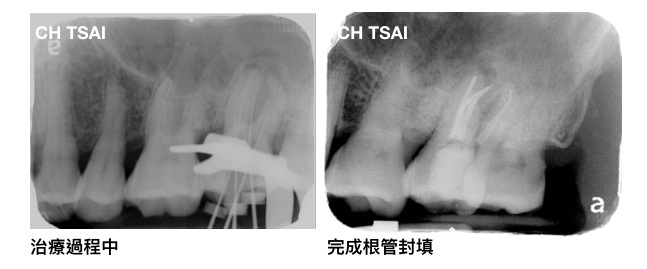

找到了額外的根管後,進行根管的擴大修型,並以超音波器械震盪沖洗,治療過程中陳先生主觀的症狀也慢慢有了改善;以下為治療中的X光片。